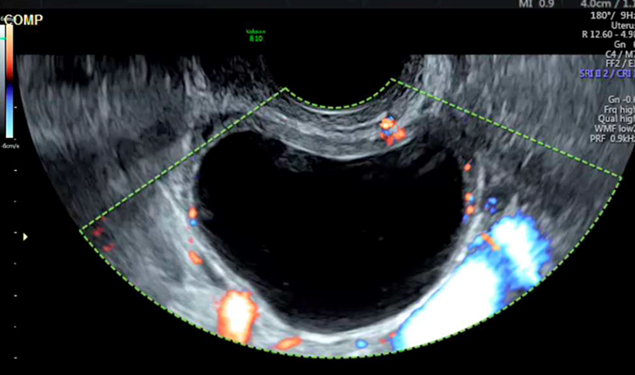

L’échographie objective l’image suivante (fig. 3) de 60 mm de grand axe au niveau de l’ovaire droit.

Figure 3 (Rodolphe Matias de Sousa, La Revue du Praticien)

Question 5 - Qu’en pensez-vous (une ou plusieurs réponses exactes) ?

Vous êtes devant un tableau typique de kyste fonctionnel. Il faut contrôler sa disparition à trois mois. Si le kyste persiste il faudra discuter d’une kystectomie. On peut proposer une contraception œstroprogestative en continu afin de bloquer l’ovulation en attendant.

Il n’y a pas de vascularisation périphérique anarchique sur cette image. Le gros vaisseau prenant le signal Doppler correspond à l’artère iliaque interne.

On ne réalise une IRM pelvienne qu’en cas de kyste suspect de malignité ou organique. Il n’est pas recommandé d’en réaliser une pour un kyste uniloculaire fonctionnel inférieur à 70 mm. Les marqueurs à prélever en cas de lésion suspecte sont : CA 125, CA 19-9, ACE.

Les différents critères échographiques permettant de s’orienter face à un kyste ovarien sont résumés dans le tableau 2 :